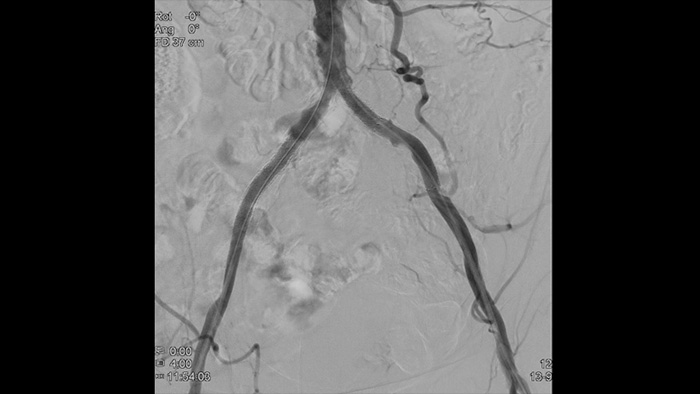

Imágenes de alta definición de los vasos con detalles vasculares superiores para apoyar estrategias de tratamiento precisas, navegación y seguimiento.

VesselNavigator proporciona una hoja de ruta 3D intuitiva y continua basada en conjuntos de datos de CTA y MRA existentes para guiarlo a través de la vasculatura durante los procedimientos periféricos.